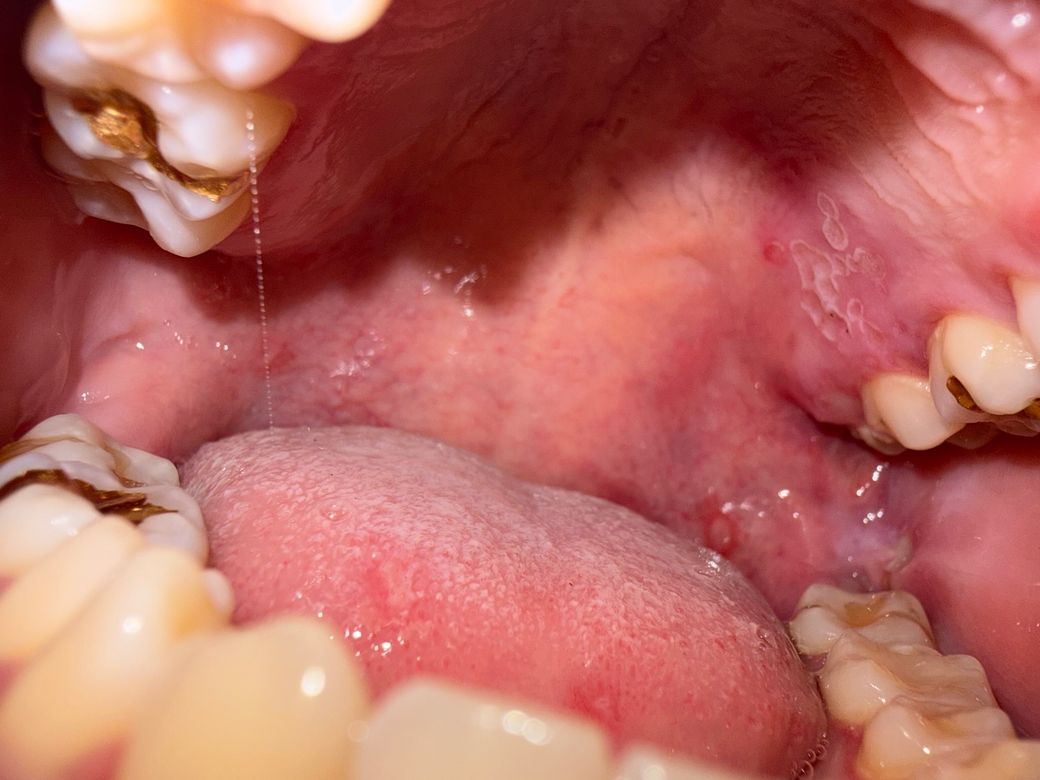

세번째가 현재 입니다

• 3번 째 사진

목젖 부위가 2, 3번 사진에서는 나와 있지는 않으니 전반적으로 호전되었는지 알기는 다소 어렵습니다. 오른쪽 아래 1개 있는 것은 변화를 볼 수 있는데, 큰 호전은 없는 것 같아요. 가장 중요한 것은 증상의 호전입니다. 안 아프면 좋아지고 있는 것이라고 볼 수 있지요.

• 사진상으로는 연구개와 구개궁 주변에 국소적인 발적과 작은 궤양성 병변이 보입니다. 전형적인 아프타성 구내염(apthous ulcer) 또는 경미한 바이러스성 인두염에서 흔히 보이는 소견과 유사합니다. 농성 삼출물이나 편도 비대, 뚜렷한 화농성 소견은 두드러지지 않습니다.

구내염은 시간대에 따라 뚜렷하게 악화·호전이 반복되는 질환은 아닙니다. 하루 중 통증 강도는 침 분비, 음식 자극, 피로도에 따라 달라질 수 있으나 병변 자체가 몇 시간 단위로 급격히 나빠지거나 좋아지는 경우는 드뭅니다. 일반적으로 1일에서 2일 사이 크기와 통증이 증가한 뒤 7일에서 14일 사이 자연 호전되는 경과를 보입니다.

사진 비교상 급격한 진행이나 궤양 확대, 화농성 변화는 뚜렷하지 않아 명확한 악화로 보이지는 않습니다. 현재 통증 강도가 비슷하고 발열이 없다면 급성 세균성 편도염 가능성은 낮아 보이며, 이미 항생제를 복용 중이라면 추가적인 항생제 증량이나 변경이 즉시 필요한 상황으로는 보이지 않습니다.